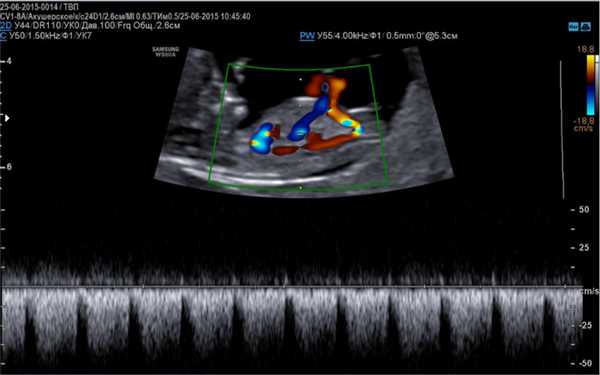

- Доплер эхокардиография, более расширенная методика, определяющая гемодинамику, ритмичность и сократительную способность сердца, направленность тока крови по сосудам.

Данные виды исследования также позволяют оценить количество циркулирующей крови, степень сужения артерий, минутный выброс, что является важным диагностическим критерием в диагностике патологий сердца.

- Допплерэхокардиография - используется для изучения гемодинамики в сосудах и камерах сердца, а также оценки сердечного ритма. Проводится в режиме ЦДК и импульсной допплерографии.